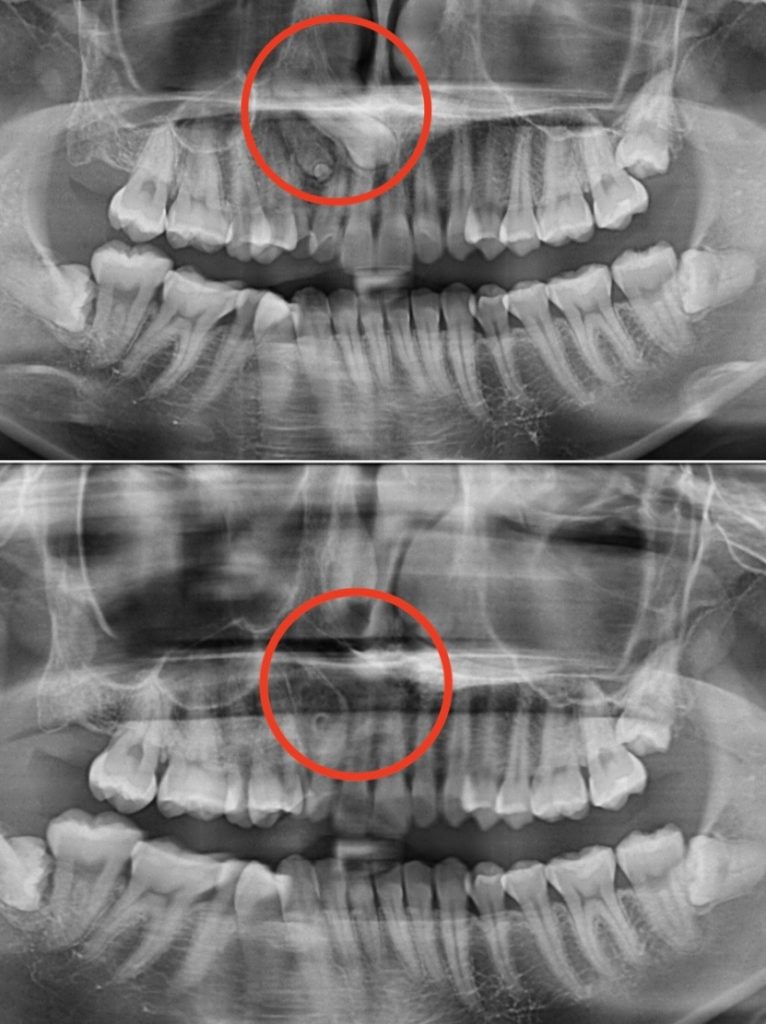

診察してみると…なんと、過剰歯が複数本あり、かなり難しい抜歯ケースでした💦

過剰歯とは、通常の本数より多く生えてしまう歯のことです。1本だけの場合もありますが、今回のように複数本ある場合は、👿歯並びが悪くなったり、👿矯正治療をスムーズに進める妨げになったりします。

さらに、奥深くに隠れている歯は、普通の抜歯よりも技術と慎重さが求められます⚡

当院ではまず、精密な診査とレントゲン検査を行い、過剰歯の位置や根の状態を確認します🔍。